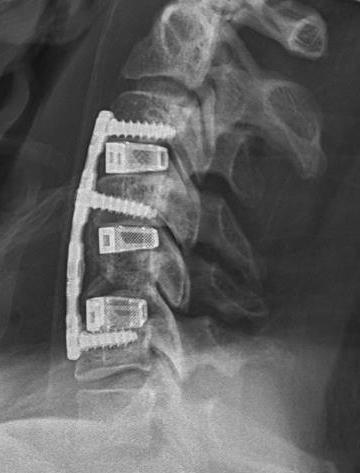

ACDF

Indication

Anterior cord compression

Single or double level compression

Kyphotic deformity

Advantages

Removes entire disc

Maintain / restore lordosis

Disadvantages

Difficulty decompressing the nerve roots in foramen

Difficult to decompression vertebral bodies

Relatively contra-indicated with OPLL

Corpectomy

Concept

Can remove body with disc above and below and decompress multiple levels

- multilevel disease

- soft and hard disc causing compression

- kyphotic deformity